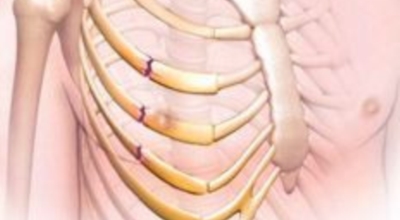

왼쪽 갈비뼈 아래 통증 - 골절

갈비뼈는 생각보다 팔과 다리 외에 가장 흔히 골절되는 부위입니다. 사소하게 기침이나 기지개를 펴다가도 부러지기도 하는데 심지어 자신도 모르는 사이에 금이 가기도 하고 골절이 나타난 경우 통증이 나타날 수 있어요. 갑작스럽게 기침을 하거나, 기지개를 켜다가도 부러질 수 있는 만큼 쉽게 골절이 되기 때문에 주의하셔야 합니다.